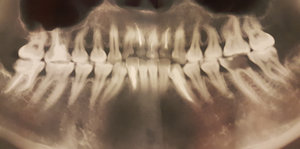

На каких зубах существует вероятность пульпита? 2. Есть ли вероятность, что на снимке присутствуют зубы, такие, что зуб значительно разрушен (от четырёх поверхностей), поэтому здесь требуется восстановление. То есть речь идёт о ситуации кариеса, когда пострадало более трёх поверхностей. Как известно, любой зуб имеет пять поверхностей (1. С внешней стороны. 2. С внутренней стороны (со стороны языка). 3. Со стороны левого соседнего зуба. 4. Со стороны правого соседнего зуба. 5. С жевательной стороны. Я понимаю, что точно диагноз нельзя поставить только по снимку, потому что нужен и визуальный осмотр, но речь идёт просто о возможности (подозрительных зубах и наиболее сложных).

Прям четких пульпитных явлений на снимке я не увидел. Шестой зуб сверху (26), требует установки коронки из-за большого количества пломбы, что по показаниям требуется реставрация вкладкой и коронкой. Не знаю про какой зуб идёт речь, но при разрушении коронковой части зуба более, чем на 50%, необходимо устанавливать коронки. Для более подробной консультации, обратитесь к стоматологу на очный приём.